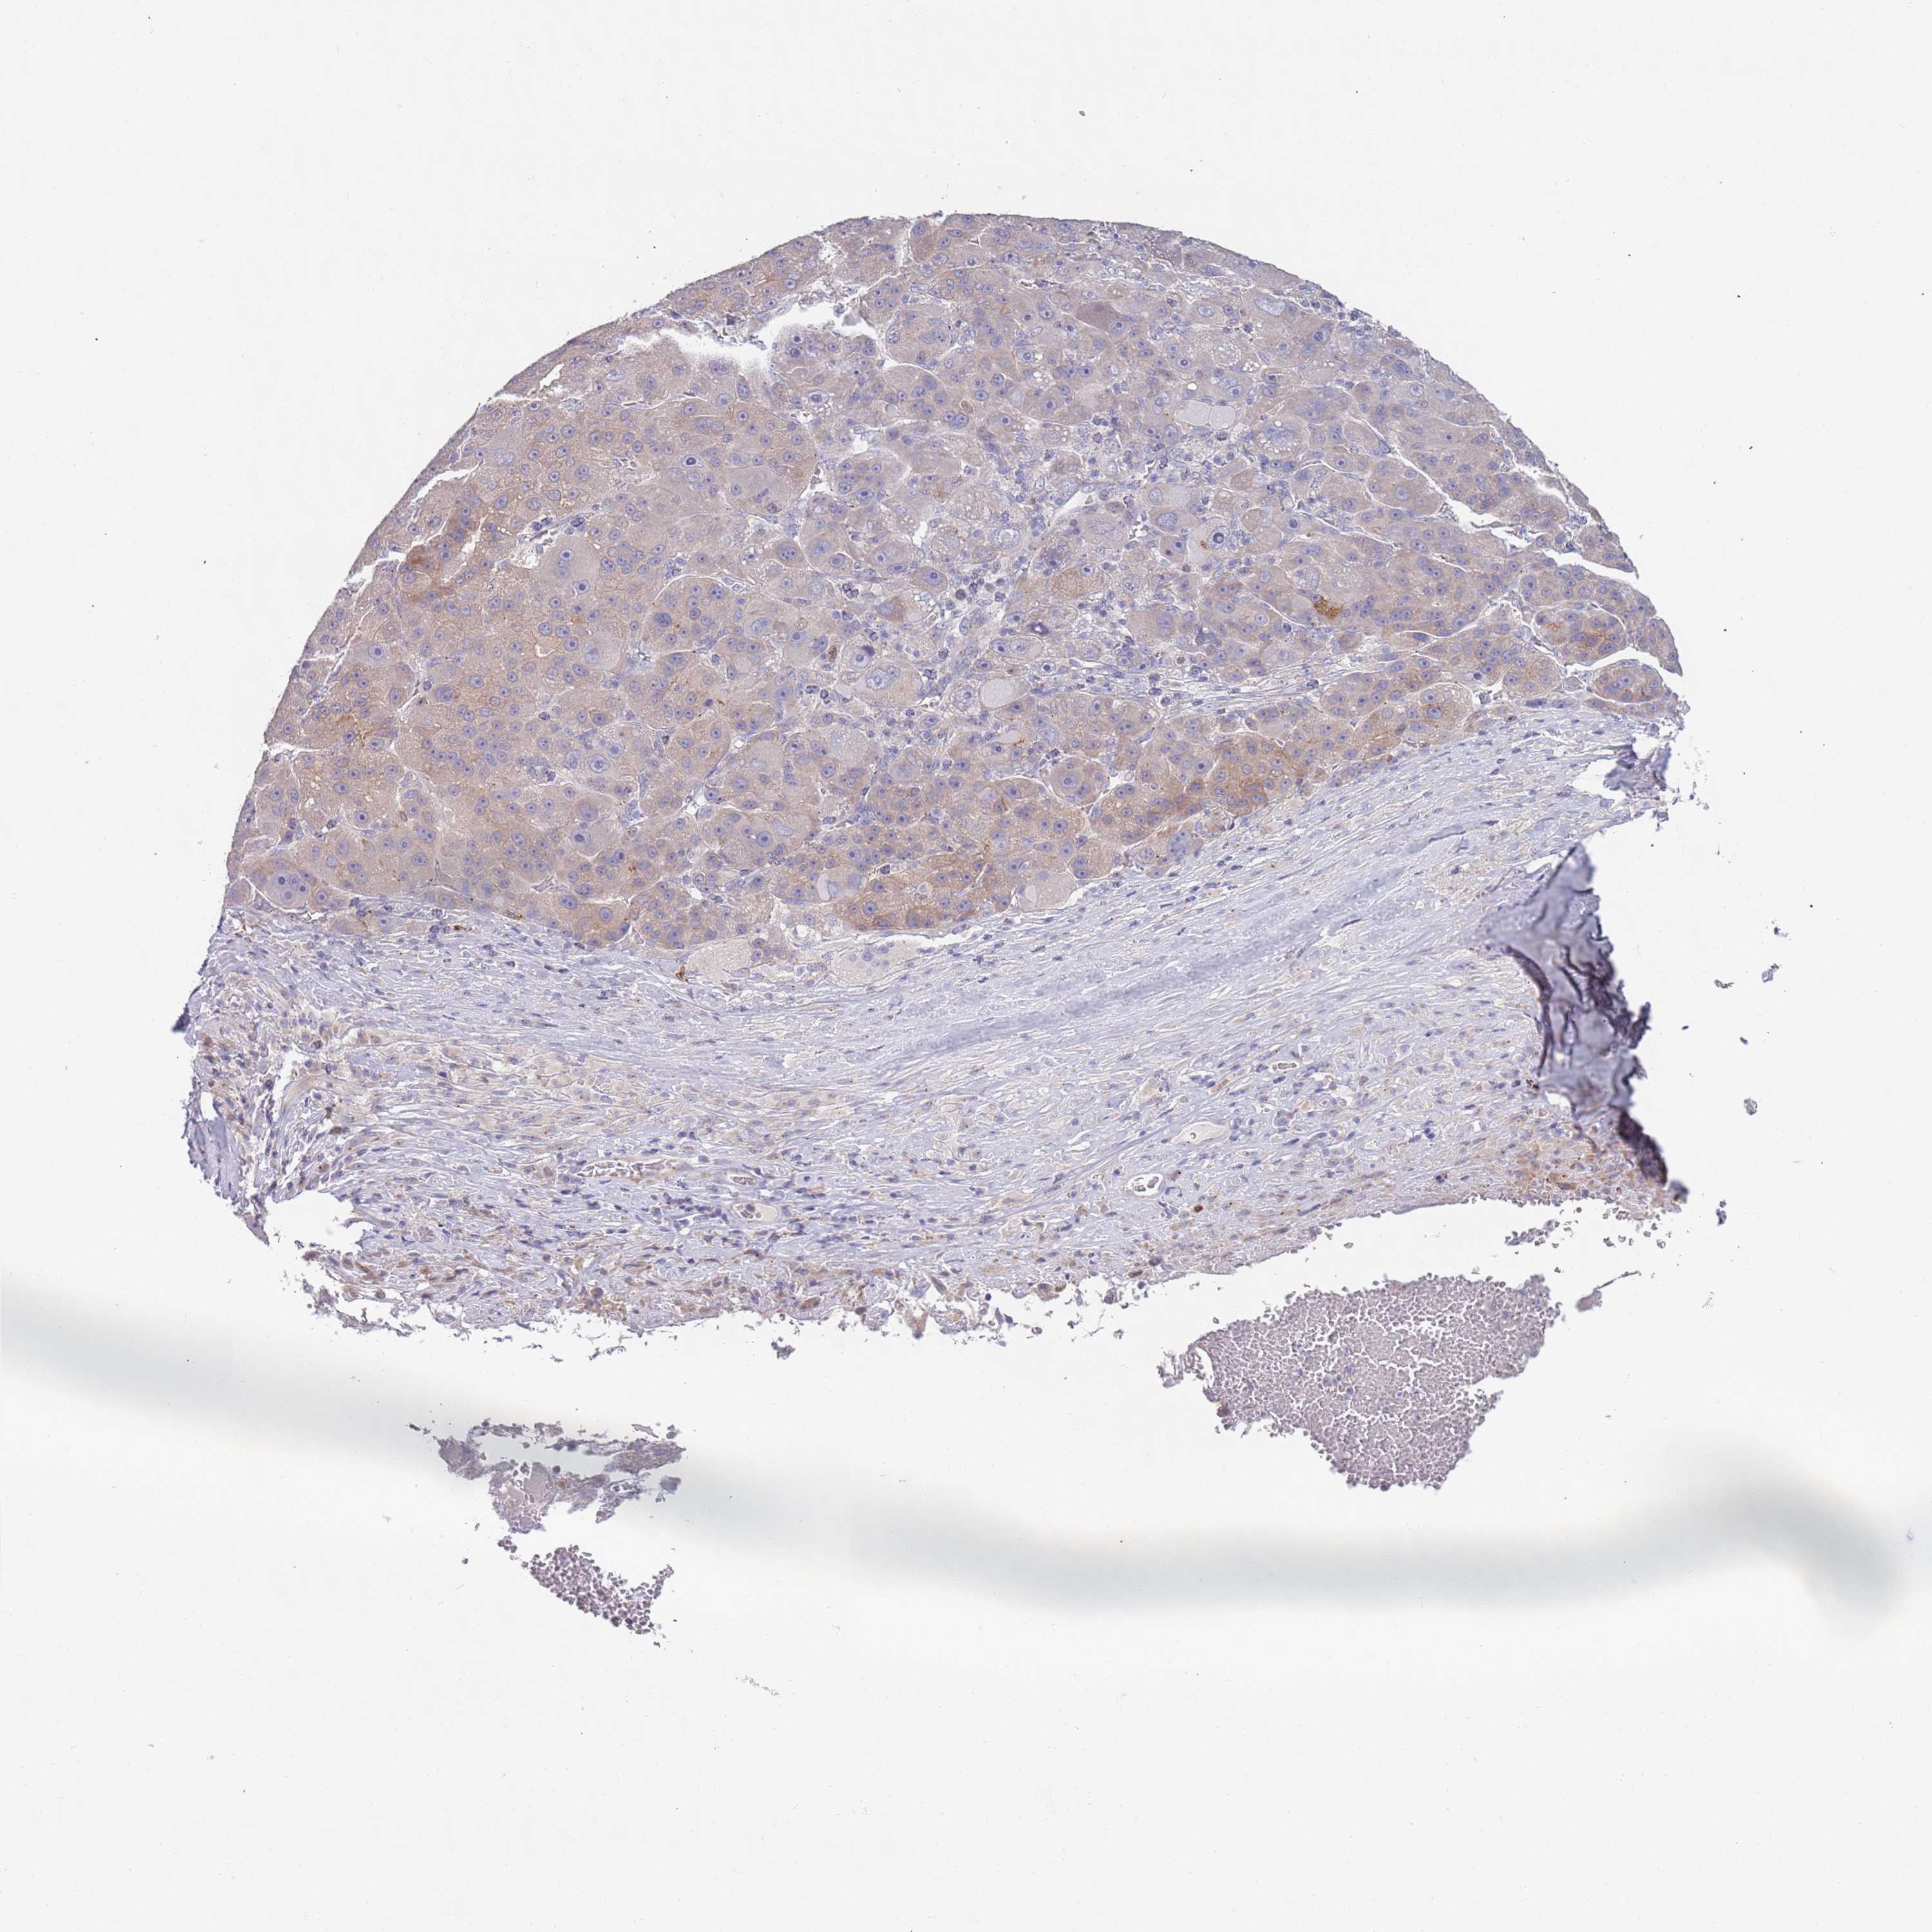

LIVER CANCER - Protein expressioni

A mouse-over function shows sample information and annotation data. Click on an image to view it in a full screen mode. Samples can be filtered based on level of antibody staining by selecting one or several of the following categories: high, medium, low and not detected. The assay and annotation is described here.

Note that samples used for immunohistochemistry by the Human Protein Atlas do not correspond to samples in the TCGA dataset.

Antibody stainingi

Antibody staining in the annotated cell types in the current human tissue is reported as not detected, low, medium, or high, based on conventional immunohistochemistry profiling in selected tissues. This score is based on the combination of the staining intensity and fraction of stained cells.

Each image is clickable and will lead to virtual microscopy that enables deeper exploration of all samples and also displays staining intensity scores, fraction scores and subcellular localization as well as patient and tissue information for each sample.

Antibody HPA048884

Staining

High

Medium

Low

Not detected

Intensity

Strong

Moderate

Weak

Negative

Quantity

>75%

75%-25%

<25%

None

Location

Nuclear

Cytoplasmic/membranous

Cytoplasmic/membranous,nuclear

Cholangiocarcinoma

Carcinoma, Hepatocellular, NOS